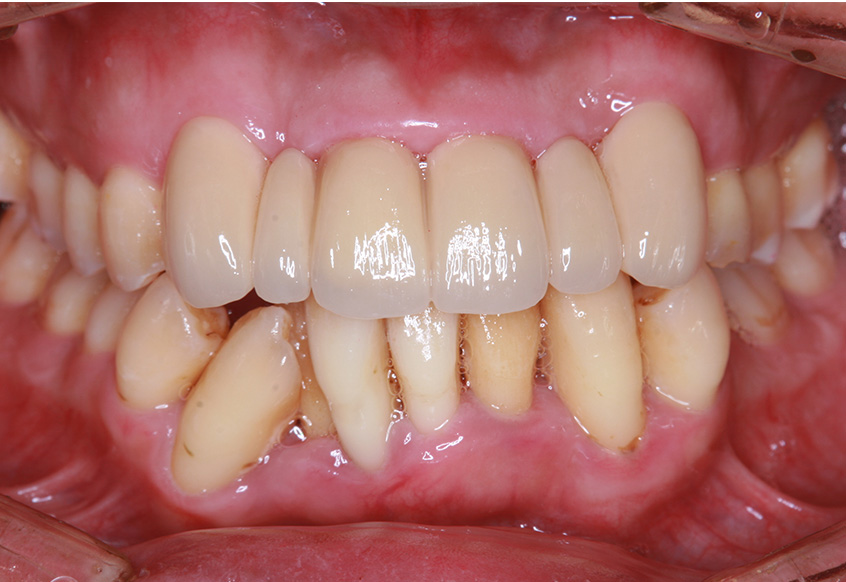

マウスピース(インビザラインGo)による矯正治療(下顎)

術前・術後の比較

治療の概要

| 患者属性 | 30代女性 |

|---|---|

| 主訴 | 下の前歯1本がでているのが気になる |

| 診断 | 下顎歯列不正 |

| 矯正装置 | マウスピース(インビザラインGo) |

| 治療期間 | 4か月(16週) |

| 通院回数 | 初診から合わせて7回の来院 |

| 治療費 | 総額478,500円(初期費用440,000円+診察料4,400円×5ヵ月分+保定装置16,500円/個)費用は税込 |

| 治療内容 | 月1回の歯科医院での治療と日常はマウスピースを常時装着 |

| リスクと副作用 | 矯正治療

|